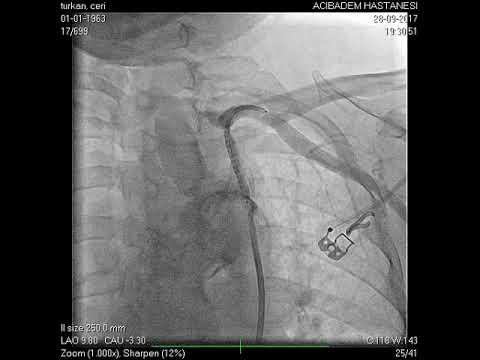

Anjiyografik İşlemler

Kapat